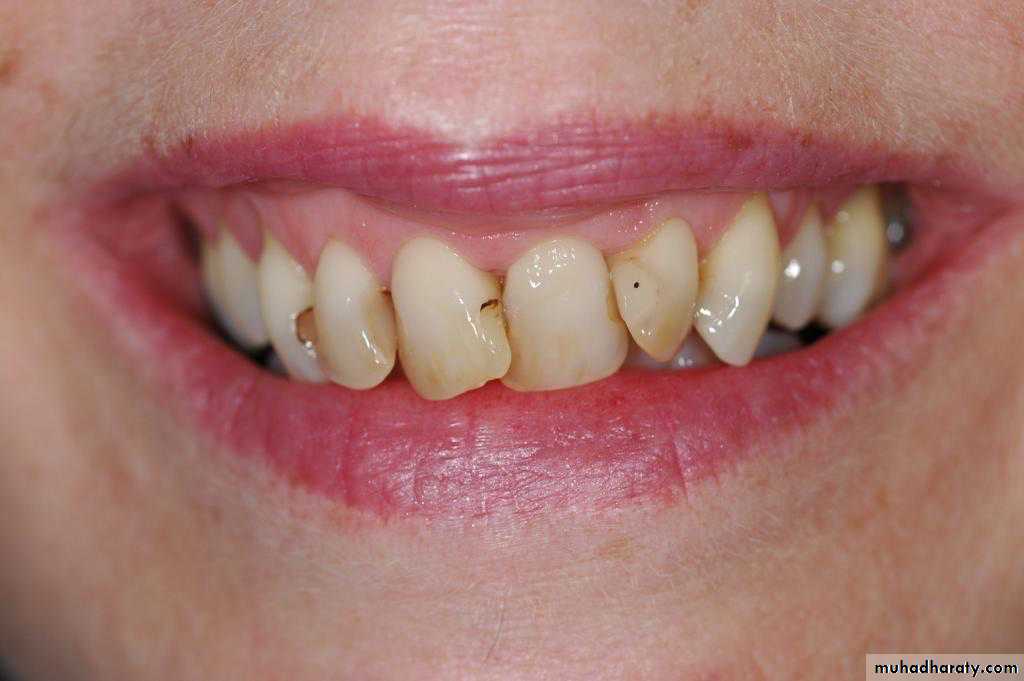

Unattractive facial esthetic.Dysfunction of TMJ.

Susceptibility to dental caries.

Susceptibility to periodontal disease.

1.dentalcaries, impacted , trauma , periodontal.